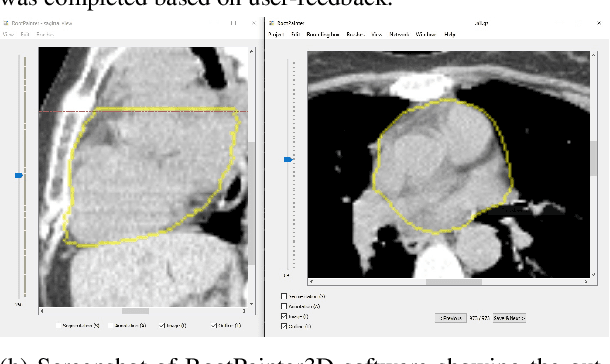

Abstract:Organ-at-risk contouring is still a bottleneck in radiotherapy, with many deep learning methods falling short of promised results when evaluated on clinical data. We investigate the accuracy and time-savings resulting from the use of an interactive-machine-learning method for an organ-at-risk contouring task. We compare the method to the Eclipse contouring software and find strong agreement with manual delineations, with a dice score of 0.95. The annotations created using corrective-annotation also take less time to create as more images are annotated, resulting in substantial time savings compared to manual methods, with hearts that take 2 minutes and 2 seconds to delineate on average, after 923 images have been delineated, compared to 7 minutes and 1 seconds when delineating manually. Our experiment demonstrates that interactive-machine-learning with corrective-annotation provides a fast and accessible way for non computer-scientists to train deep-learning models to segment their own structures of interest as part of routine clinical workflows. Source code is available at \href{https://github.com/Abe404/RootPainter3D}{this HTTPS URL}.